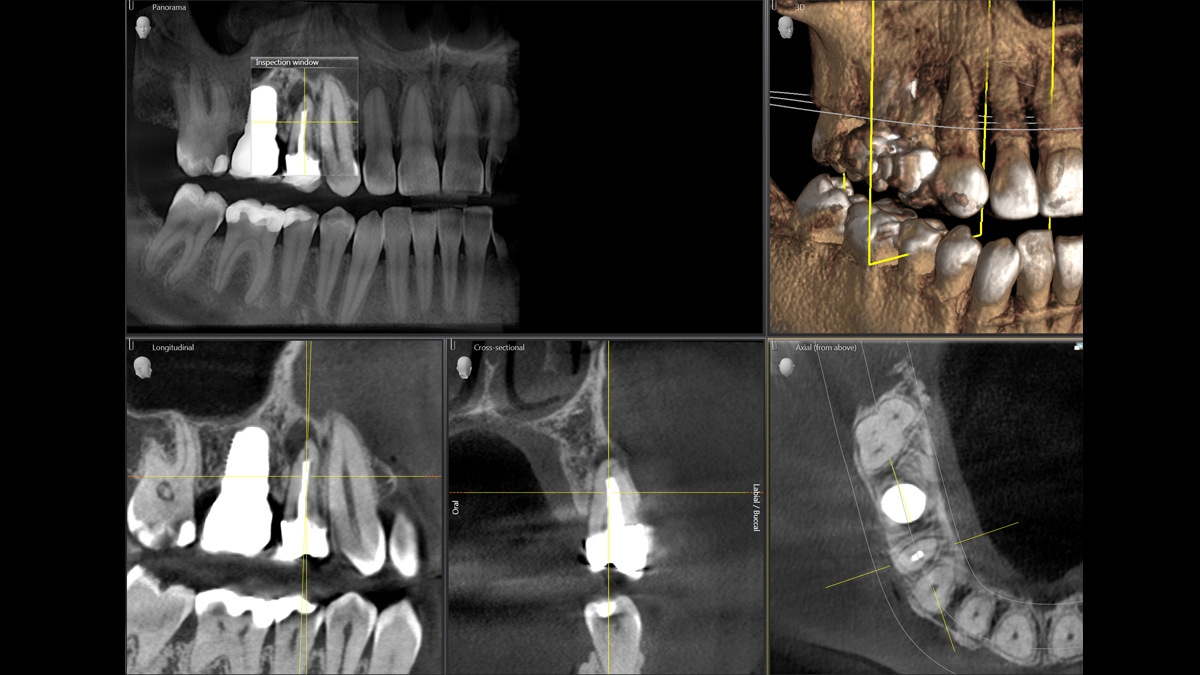

We developed a 10-point concept for easy patient positioning and X-ray imaging. Our concept is primarily about two things: high image quality and comfort for the patient and the assistant. This concept supports and provides the tools needed to ensure high-quality images for treatment analysis and focuses on ergonomics and comfort for the patient and assistant. The patented bite block technology, for example, automatically establishes the correct inclination of the patient's head, positioning the patient in the occlusal plane, partnering with the 3 point head fixation and firm handles to ensure stable positioning-limiting unnecessary correction scans.